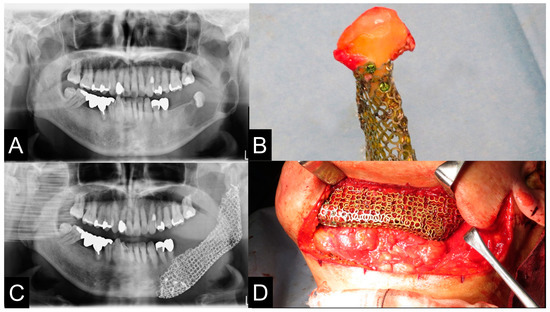

| Case | Gender | Age | Diagnosis of Primary Disease | Primary Reconstruction | Bone Defect | Classification Of Js Brown | Schematic of Mandibular Defect |

|---|---|---|---|---|---|---|---|

| 1 | M | 23 | Ameloblastic carcinoma | None | Marginal bone defects | Marginal bone defect | ![]() |

| 2 | M | 73 | SCC Gingiva | Surgical plate | Segmental bone defects | Body-chin Class II | ![]() |

| 3 | F | 78 | SCC Floor of mouth | Rectus abdominis musculocutaneous flap and surgical plate | Segmental bone defects | Body-chin Class III | ![]() |

| 4 | M | 70 | SCC Floor of mouth | Anterior cervical flap | Marginal bone defects | Marginal bone defect | ![]() |

| 5 | F | 69 | SCC Gingiva | Surgical plate | Segmental bone defects | Ramus-body Class I | ![]() |

| 6 | M | 69 | Osteoblastoma of the mandible | None | Marginal bone defects | Marginal bone defect | ![]() |

| 7 | M | 73 | SCC Gingiva | None | Marginal bone defects | Marginal bone defect | ![]() |

| 8 | M | 69 | Ameloblastoma | Simultaneous surgery | Segmental bone defects | Ramus-body Class I | ![]() |

| 9 | M | 58 | Mucoepidermoid carcinoma Floor of mouth | Vascularized fibular bone graft | Segmental bone defects | Ramus-body-chin Class III | ![]() |

| 10 | M | 60 | Ameloblastoma | Fractured surgical plate | Segmental bone defects | Ramus-body Class I | ![]() |

| 11 | F | 62 | SCC Gingiva | Fractured surgical plate | Segmental bone defects | Ramus-body Class II | ![]() |

| 12 | M | 81 | SCC Gingiva | None | Marginal bone defects | Marginal bone defect | ![]() |

| 13 | F | 50 | Odontogenic myxoma | Surgical plate | Segmental bone defects | Body-chin Class II | ![]() |

| 14 | M | 74 | SCC Gingiva | Surgical plate | Segmental bone defects | Body-chin Class III | ![]() |

| 15 | M | 62 | SCC Gingiva | Vascularized scapular bone graft (non-union) | Segmental bone defects | Body-chin Class I | ![]() |

| 16 | F | 45 | Ameloblastoma | Surgical plate | Segmental bone defects | Ramus-body Class I | ![]() |

| 17 | M | 17 | Ossifying fibroma | None | Mandibular partial resection | Marginal bone defect | ![]() |

| 18 | M | 63 | Ameloblastoma | Fractured surgical plate | Segmental bone defects | Ramus-body-chin Class III | ![]() |

| Case | Virtual Reconstruction Technique | Preoperative Simulation of PCBM Amount | The Reality of PCBM Quantity | Preoperative Length (mm) | Postoperative Length (mm) | A Preoperative Sum of the Condylar Axial Angles (Degree) | A Postoperative Sum of the Condylar Axial Angles (Degree) |

| 1 | Level 1 | 2.2 cc | 6.4 cc | 26.7 mm | 25.8 mm | 126° | 127° |

| 2 | Level 2 | 11.3 cc | 20 cc | 45.4 mm | 50.4 mm | 141° | 151° |

| 3 | Level 2 | 11.9 cc | 23 cc | 36.0 mm | 36.0 mm | 150° | 151° |

| 4 | Level 1 | 6.51 cc | 10 cc | 37.7 mm | 37.7 mm | 148° | 147° |

| 5 | Level 2 | 11.3 cc | 17 cc | 46.0 mm | 53.5 mm | 153° | 142° |

| 6 | Level 1 | 14.2 cc | 30 cc | 63.3 mm | 63.3 mm | 143° | 143° |

| 7 | Level 1 | 8.2 cc | 10 cc | 54.6 mm | 54.6 mm | 131° | 131° |

| 8 | Level 1 | 16.8 cc | 17 cc | 69.0 mm | 69.0 mm | 129° | 128° |

| 9 | Level 2 | 20 cc | 40 cc | 63.4 mm | 65.7 mm | 106° | 132° |

| 10 | Level 2 | 19.3 cc | 40 cc | 70.7 mm | 77.7 mm | 129° | 136° |

| 11 | Level 2 | 10 cc | 15 cc | 56.3 mm | 53.1 mm | 136° | 140° |

| 12 | Level 1 | 8 cc | 14 cc | 40.6 mm | 40.6 mm | 149° | 149° |

| 13 | Level 2 | 10 cc | 19 cc | 35.3 mm | 42.4 mm | 150° | 145° |

| 14 | Level 3 | 10.4 cc | 20 cc | 56.3 mm | 59.6 mm | 172° | 161° |

| 15 | Level 3 | 10.6 cc | 24 cc | 54.5 mm | 61.0 mm | 197° | 197° |

| 16 | Level 2 | 9.6 cc | 21 cc | 30.8 mm | 36.0 mm | 164° | 160° |

| 17 | Level 1 | 5.1 cc | 10 cc | 44.5 mm | 44.5 mm | 122° | 122° |

| 18 | Level 2 | 17.7 cc | 32 cc | 54.5 mm | 72.5 mm | 137° | 140° |